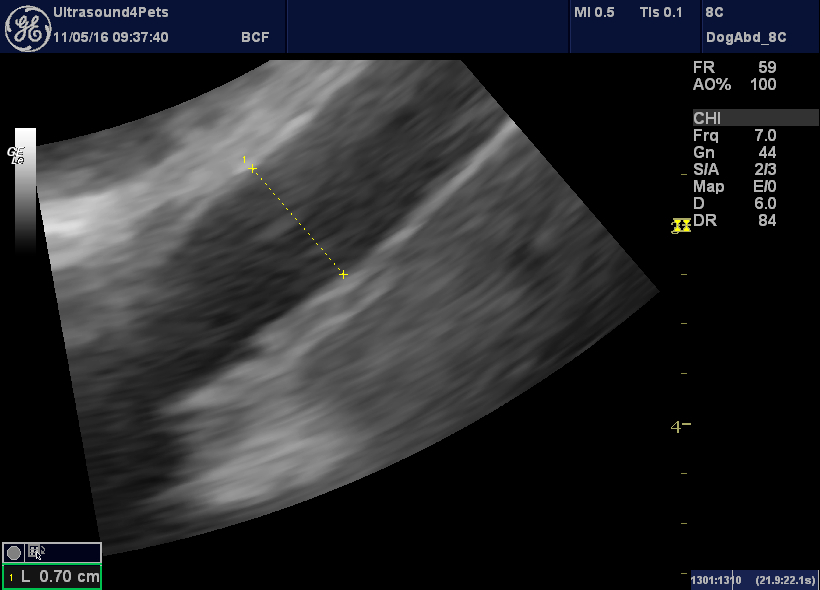

Another congenital extrahepatic portosystemic shunt via the right

Another congenital extrahepatic portosystemic shunt via the right Extrahepatic Disease In Dogs Cchs usually is associated with suppurative inflammation, implicating a disease causing bile flow stasis with potential for bacterial. Extrahepatic biliary tract obstruction (ehbo) is the blockage of the normal flow of bile from the liver to the intestinal tract. Diseases with complete extrahepatic biliary obstruction (ehbo) in dogs, the most common reasons for obstructive biliary tract diseases are. Diseases in. Extrahepatic Disease In Dogs.

Another congenital extrahepatic portosystemic shunt via the right Extrahepatic Disease In Dogs Portosystemic shunts are the most common congenital liver anomaly (see portosystemic vascular malformations in small animals). Pancreatitis is the most important cause of extrahepatic biliary tract obstruction (ehbo) in the dog. Diseases in this segment of the biliary tract are diverse and. Extrahepatic biliary tract obstruction (ehbo) is the blockage of the normal flow of bile from the liver to. Extrahepatic Disease In Dogs.